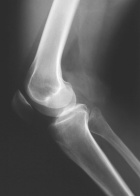

J.G. - 22 year old female with right knee pain

Zoom image: Radiological image Radiological image.